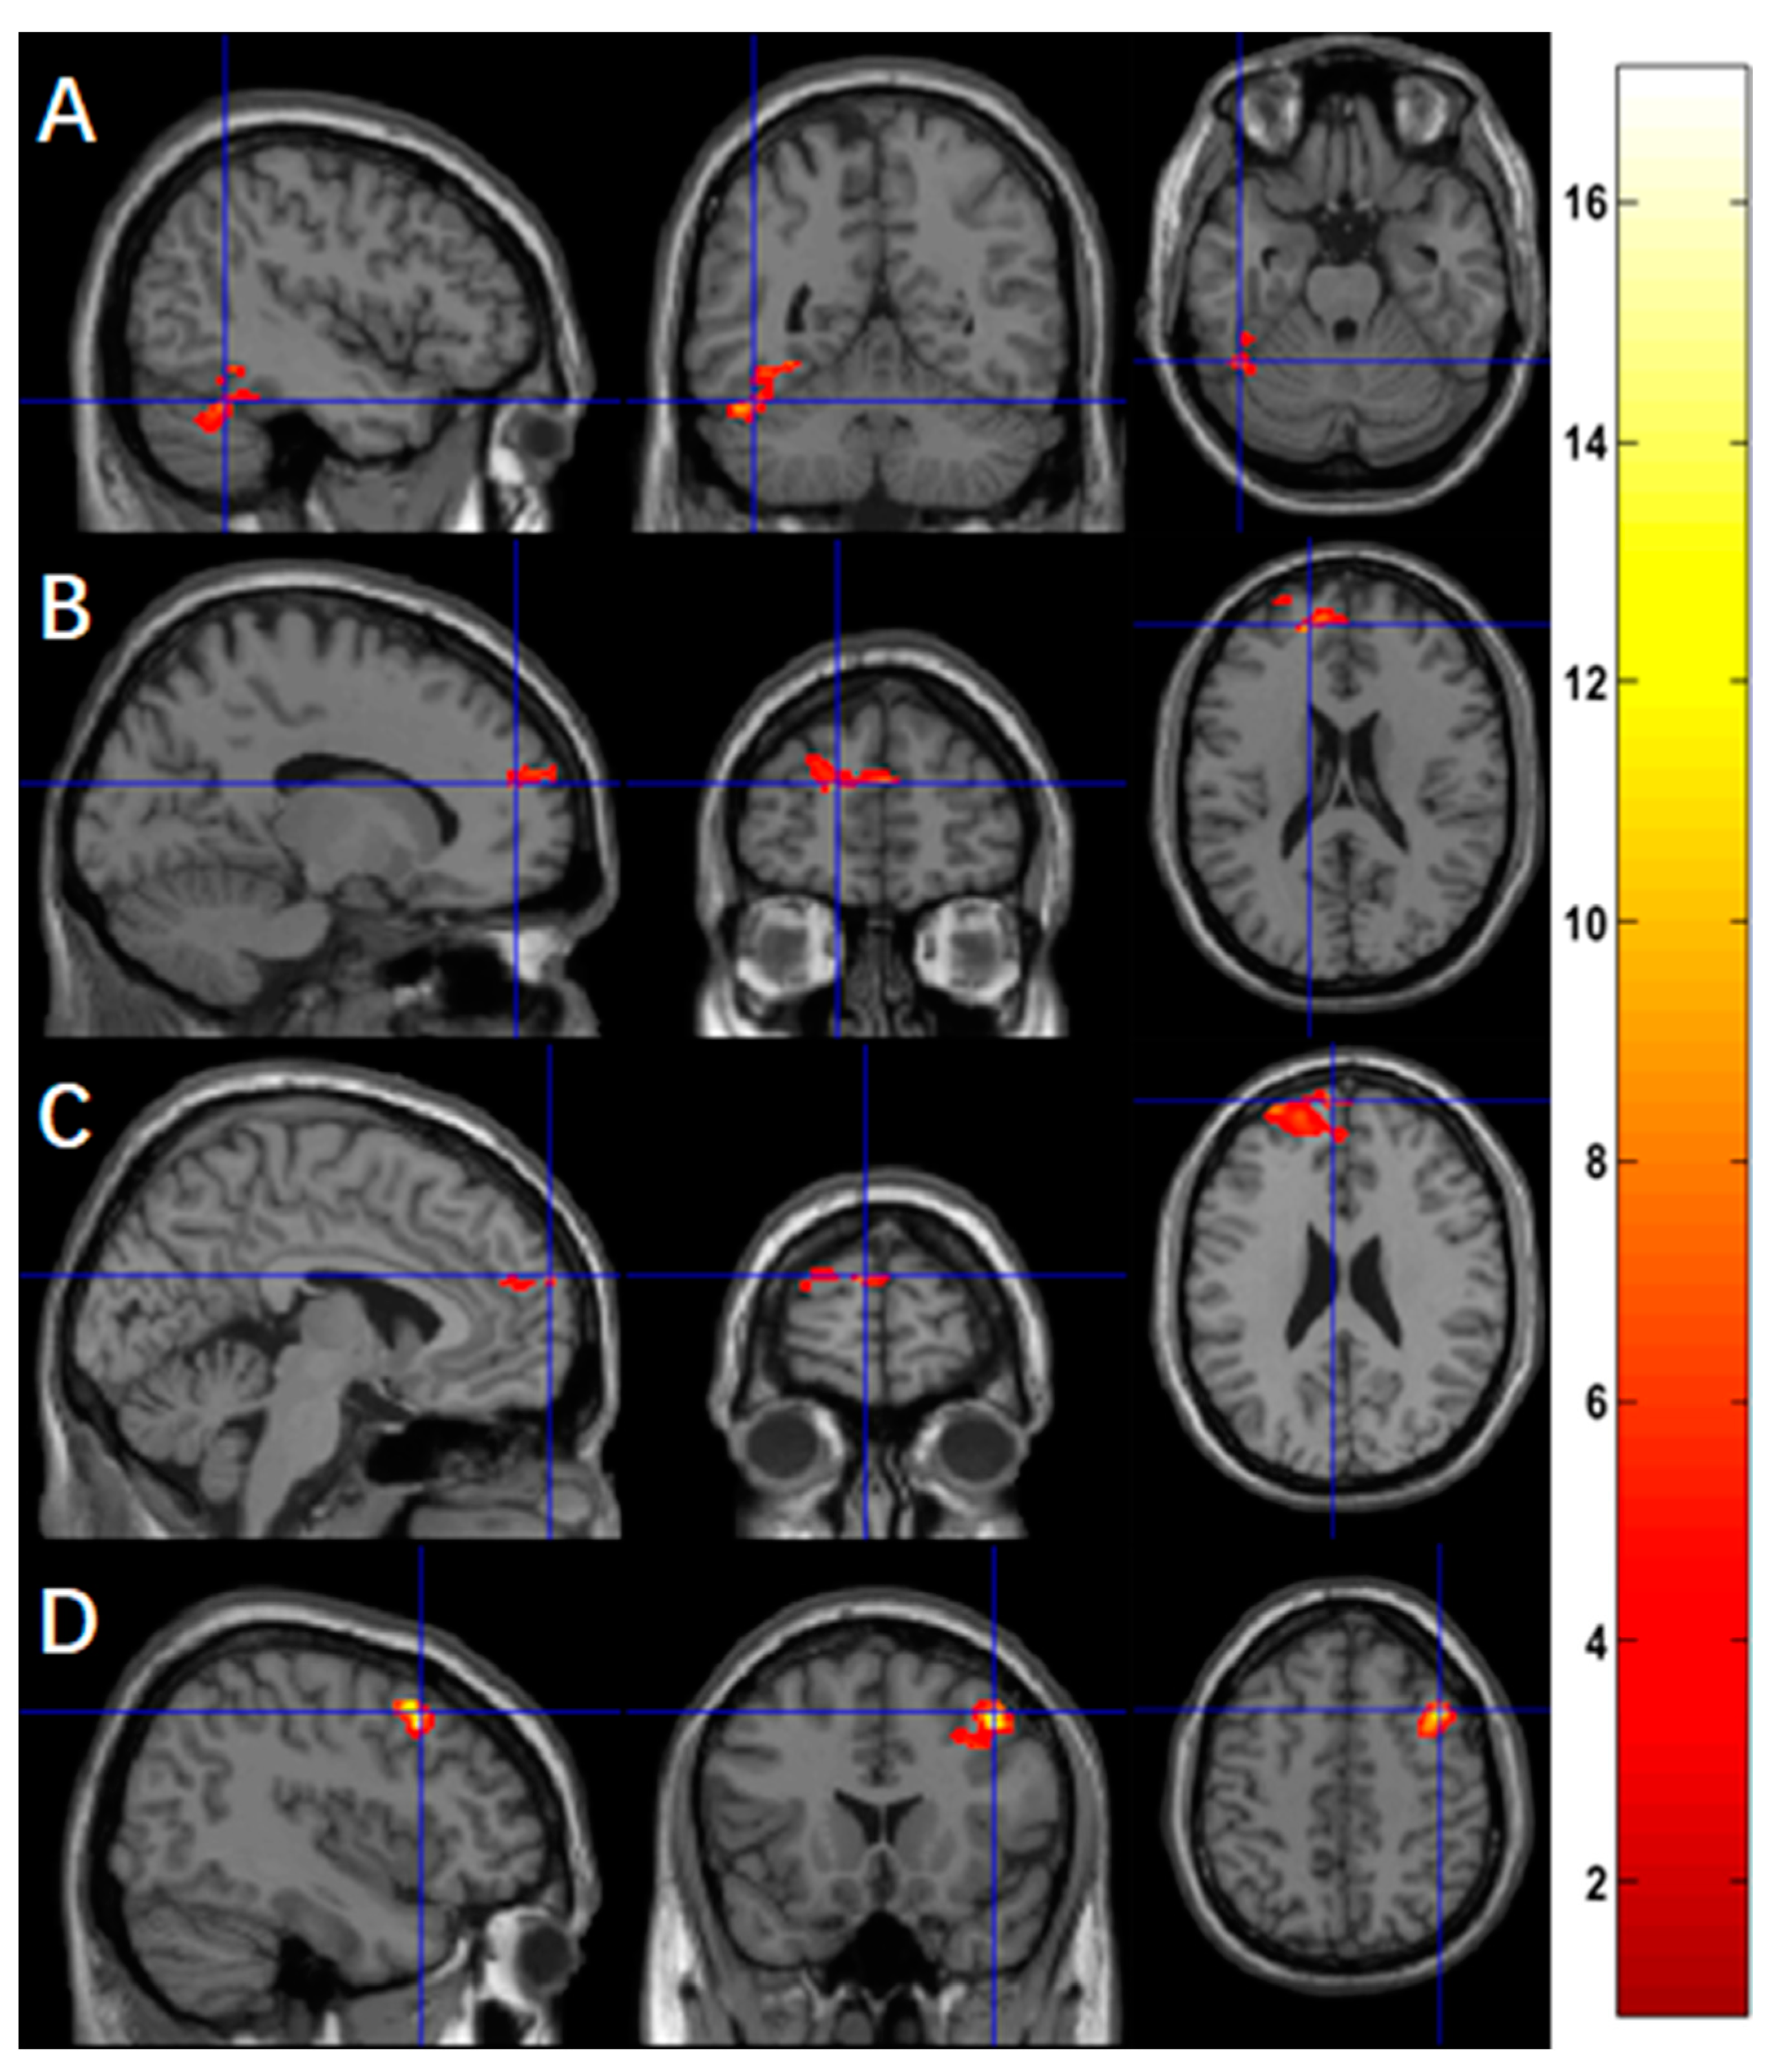

Using ASL fMRI with a voxel-level p-value of 0.005, we found significantly more activation at the two-month follow-up compared to the baseline in the middle cingulate region (cluster-level p < 10−3, Figure 1A) for the contrast of ‘X’ and in the middle cingulate region (cluster-level p = 0.004, Figure 1B) and superior temporal region (cluster-level p = 0.031, Figure 1C) for the contrast of ‘X+O’. Cluster-level statistics for the significant clusters are shown in Table 2. There were no significant changes in activation for the other contrasts. Using BOLD fMRI, no significant changes in activation were found, with a voxel-level significance threshold of 0.005. For exploratory purposes, we increased the voxel-level p-value by a step of 0.005 until we found a significant cluster. With a relaxed voxel-level p-value, we found significantly less activation at the two-month follow-up compared to the baseline in the occipital region (voxel-level p = 0.040, cluster-level p = 0.030, Figure A1A) for the contrast of ‘X’, and in the occipital region (voxel-level p = 0.010, cluster-level p = 0.048, Figure A1B) for the contrast of ‘X+O’. Cluster-level statistics for the significant clusters are shown in Table A1.

Figure 1.

Using ASL fMRI (n = 9), regions overlaid on a standard brain template in which significantly increased functional activation after a 2-month meditation training was observed with a voxel-level p-value of 0.005 in (A) the middle cingulate region for the contrast of ‘X’, (B) the middle cingulate region, and (C) the superior temporal region for the contrast of ‘X+O’, and (D) increased functional activation for the clusters in (A–C) from the baseline to follow-up.